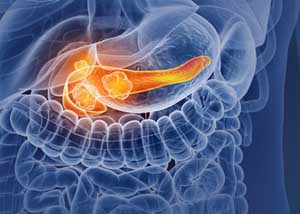

췌장은 위장의 뒤쪽 몸통의 중앙에 붙어있고 있었고 위, 십이 지장, 소장, 대장 등의 장기에 둘러싸여 있어서 췌장암을 초기 발견하는게 정말 쉽지 않습니다 췌장암의 90% 이상은 췌관의 외분비 세포에 암이 전파되어 선암으로 예사로 췌장암입니다.

췌장암 초기증상 - 황달

황달은 췌장머리췌장 머리 부분에 위치하고 있는 종양이 총담관에서 소장으로 계속되는 부분을 폐쇄하여 담즙의 흐름을 억제해 혈액 내 빌리루빈 수치가 상승해서 생기는 것으로, 췌장 머리 부분에서 일어나는 암의 약 80%에 있죠. 몸통이나 꼬리에 종양이 생성한 경우에는 5~6% 정도만 황달이 나타나는데, 거의 황달이 생겨날 때는 이미 암세포가 췌장 전체에 퍼져 간이나 림프절로 전이될 정도로 병이 진전된 상태가 많답니다. 혈액 내 빌리루빈 수치의 상승으로 황달이 나타난 경우에는 피부와 눈의 흰자위가 노란색으로 변하고, 소변 색이 갈색으로 되며 피부의 가려움증이 유발되요.